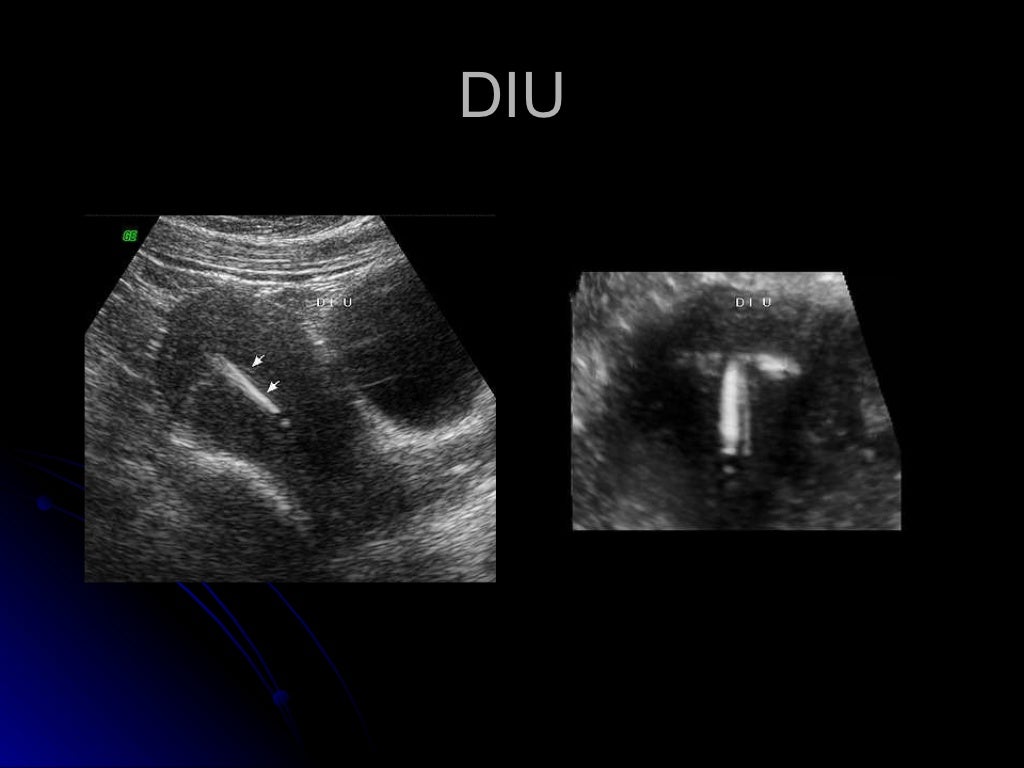

Ultrasonido pelvico

Source: es.slideshare.net